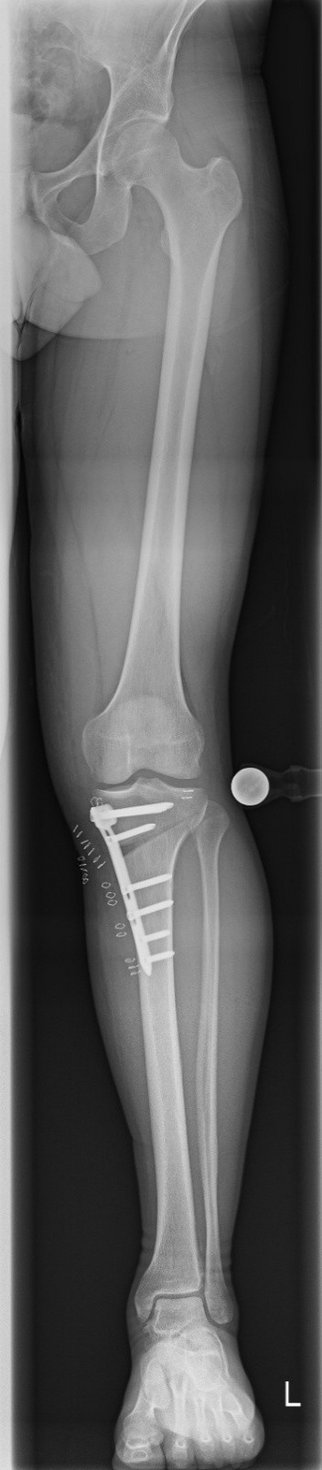

Tibiakopf Fraktur

Die arthroskopisch assistierte Frakturversorgung (insbesondere am Tibiakopf) im Rahmen von Band- bzw. Kombinationsverletzungen ist ebenfalls ein Schwerpunkt der Abteilung. Der ärztliche Direktor PD Dr. med. Schlumberger ist im DKG-Komitee „Frakturen“ vertreten.

Beinachsfehlstellungen

Manchmal liegen Beschwerden Fehlstellungen zu Grunde – sei es im Sinne eines „O-Beins“ bzw. eines „X-Beins“, aber auch eine Rotationsfehlstellung kann ursächlich für Beschwerden des Kniegelenkes sein. Gerade bei Knorpelschädigungen und Arthrose ist eine Fehlstellung mit konsekutiver Überlastung einer Gelenkhälfte oftmals ursächlich. Durch den Ausgleich der Fehlstellung wird die Biomechanik des Gelenkes wieder hergestellt und das betroffene Areal entlastet. Wir bieten Umstellungen in allen Ebenen (O-Bein, X-Bein, Rotationsfehlstellungen, pathologischer Slope, …) an. Oft ist es sogar möglich, dass eine notwendige endoprothetische Versorgung nochmals lange hinausgezögert werden kann, was vor allem jungen Patienten zu Gute kommt.